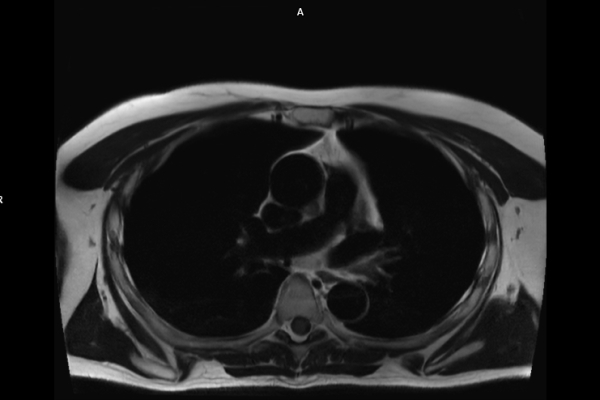

CT Untersuchung Bild

Die MRT (Magnetresonanztomographie) arbeitet mit Magnetfeldern und Radiowellen und eignet sich besonders für Untersuchungen der Weichteile wie Gehirn, Muskeln oder Gelenke. Die CT (Computertomographie) nutzt Röntgenstrahlen und liefert schnelle, hochauflösende Bilder, insbesondere für Knochen, Lunge oder innere Organe. Die Wahl der jeweiligen Untersuchung richtet sich an das individuelle Krankheitsbild und wird bei der Überweisung festgelegt.